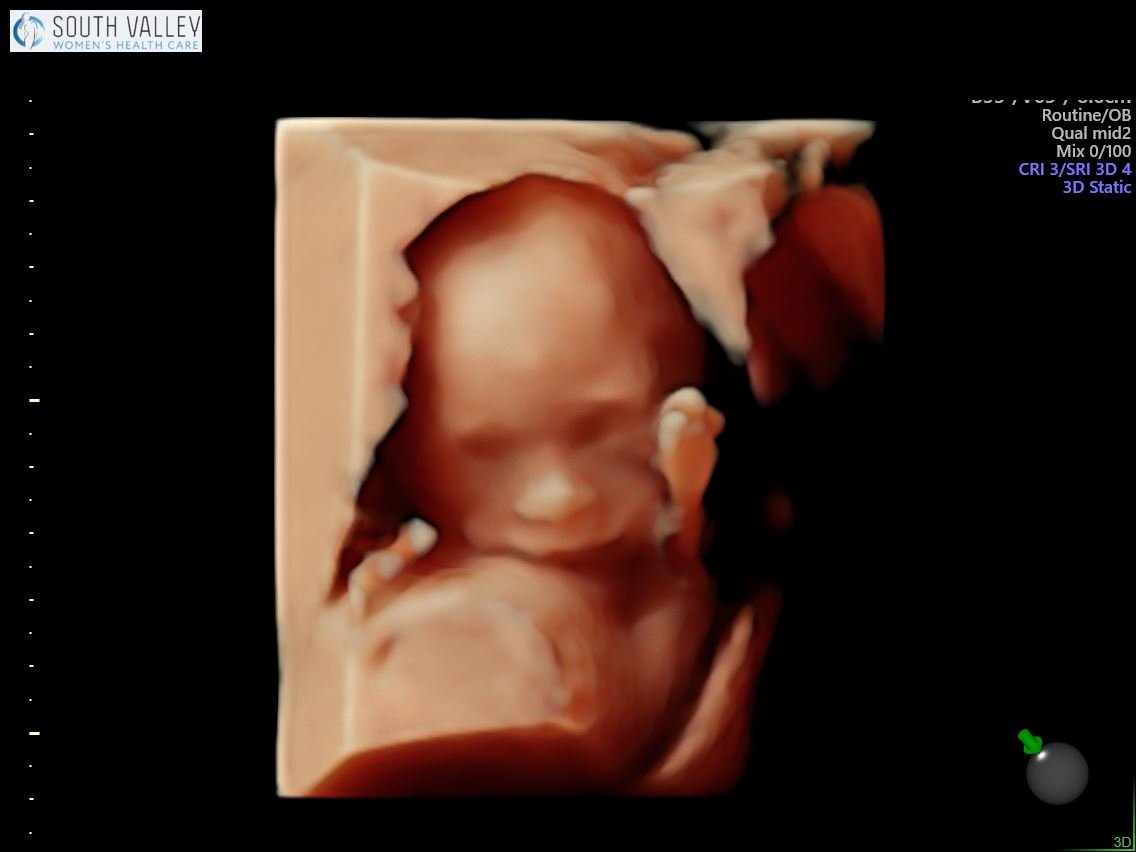

Yesterday we had our anatomy scan and it went well! Everything is looking perfect so far — the brain, the heart, all of those internal organs are in the right place and best of all, I got to see some of he sweetest shots of his cute little face! If you’ve ever wondered what a 19 week old baby in pregnancy looks like, here you have it. She said it’s rare that she gets a face shot this good at such an early age so I was pretty happy about that!

19 Week Ultrasound